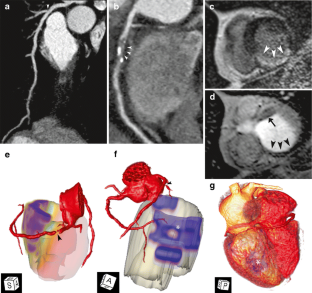

Surface representations and volume-rendered images from fused CTCA/CMR data of five patients with significant coronary artery disease (CAD) on CTCA and perfusion deficits on CMR were generated using a newly developed software prototype. The spatial relationship of significant coronary artery stenosis at CTCA and myocardial defects at CMR was evaluated.

Registration of CTCA and CMR images was possible in all patients. The comprehensive three-dimensional visualisation of fused CTCA and CMR data accurately demonstrated the relationship between coronary artery stenoses and myocardial defects in all patients.

Fig. 1